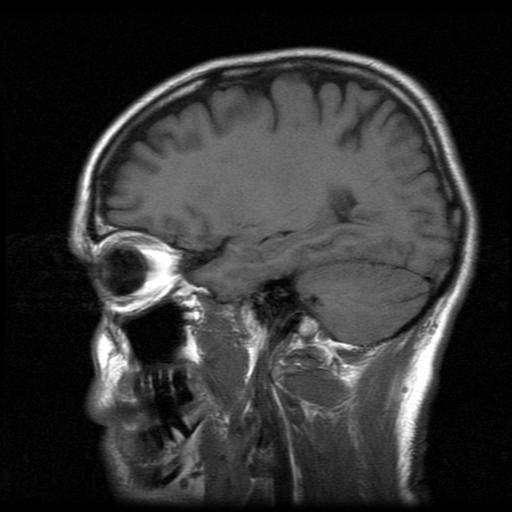

La ciencia se ha dedicado a fondo a estudiar al órgano más complejo del cuerpo: el cerebro, a pesar de ello hay muchas cosas que aún no sabemos. En lo referente al amor y sus efectos hay diversos estudios que aseguran que eso que llamamos "estar enamorados" es producto de la actuación de muchas hormonas que trabajan en simultáneo

Los adictos a las relaciones y los dependientes emocionales lo saben: el amor puede ser adictivo, ésto se debe a que durante el enamoramiento bajan los niveles de serotonina y aumentan los de dopamina produciendo un placer similar al que se recibe con el consumo de algunas drogas, por eso deseamos más y más estar con esa persona

Las áreas vinculadas con la recompensa de dopamina están a tope con este neurotransmisor mientras aquellas partes del cerebro relacionadas con el juicio crítico y las emociones y pensamientos negativos tienen poca actividad, de allí que durante el enamoramiento sea difícil detectar que esa persona no es para nosotros

Además la ciencia hizo un descubrimiento interesante: mientras más hacemos el amor con esa persona que nos vuelve locos nuestro cerebro segrega oxitocina que es la hormona responsable de que querramos establecer relaciones a largo plazo y comprometernos

El aumento en los niveles de oxitocina hace que tengamos mayor confianza hacia esa persona, que nos sintamos apegados y que deseemos pasar mucho tiempo en su compañía. Mientras más oxitocina hay más ganas de un futuro juntos se experimentarán

Es decir que la atracción, el enamoramiento, la felicidad, las ganas sexuales, la sensación adictiva de querer más y más y hasta el deseo de pasar el resto de nuestros días al lado de esa persona es producto de un gran cóctel de hormonas cortesía de nuestro cerebro y su complejo funcionamiento